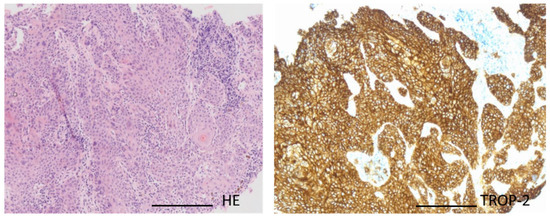

- mRNA sequencingMessenger RNA (mRNA) is transcribed from the DNA sequence of genes and then translated into proteins. Therefore, sequencing mRNA is considered as a more direct measure of the effect of DNA changes on protein products [2]. RNA analysis yielded two relevant results: 117-fold overexpression of Trop-2 (also called TACSTD-2) and 8-fold overexpression of PVRL4 (also called Nectin).